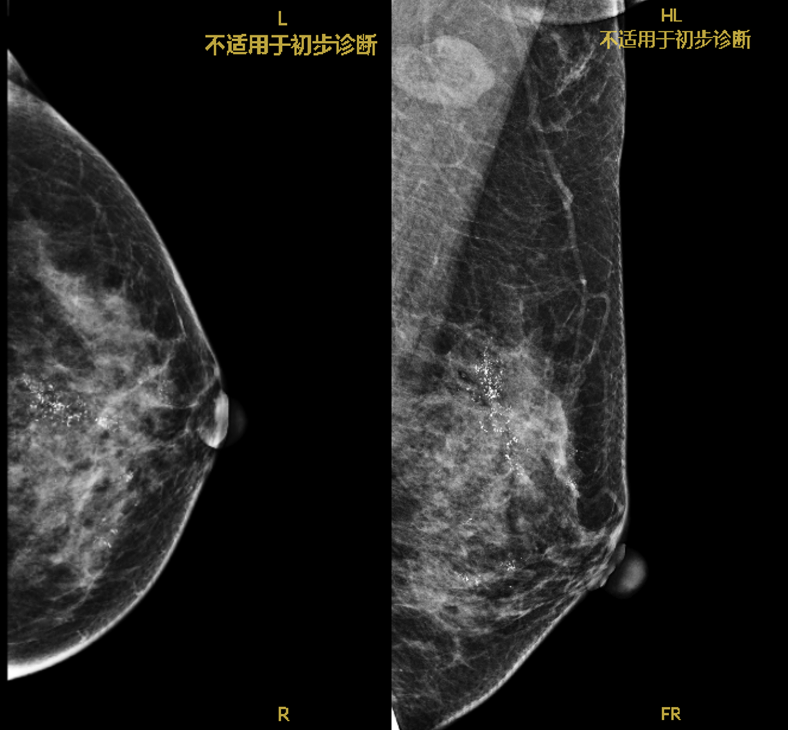

术前我院钼

靶提示:左乳癌治疗后,左乳可见多发簇状、区域性分布粗糙不均质钙化,范围较大者位于上方,范围为4.3×1.8cm。

术前钼钯